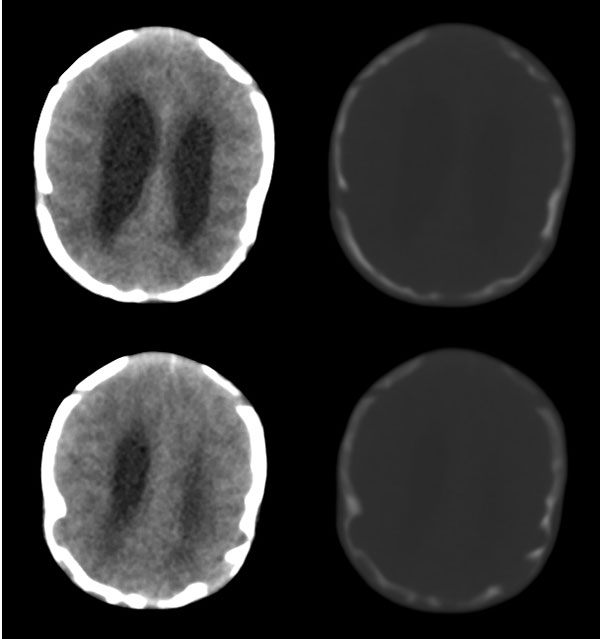

枕骨缺损,脑膜脑膨出。同时第4脑室挤压变形、闭塞,致使第3脑室、双侧侧脑室显著积水、扩张,过高的颅内压推挤脑实质,致使颅骨内板出现多而且深的脑回样压迹,脑细胞水肿,皮质、白质分界不清。

颅骨内面凹陷——过高的颅内压推挤脑实质,过高的颅内压推挤脑实质,致使颅骨内板出现多而且深的脑回样压迹

从图像分析看到的是三、侧脑室的积水,颅骨凹凸不平应是脑压高引起的,脑膜膨出是因脑压增大所致。综合考虑是:中脑水管发育畸形(狭窄或闭锁不全)并三、四脑室积水。枕骨发育不全伴脑脊膜膨出。